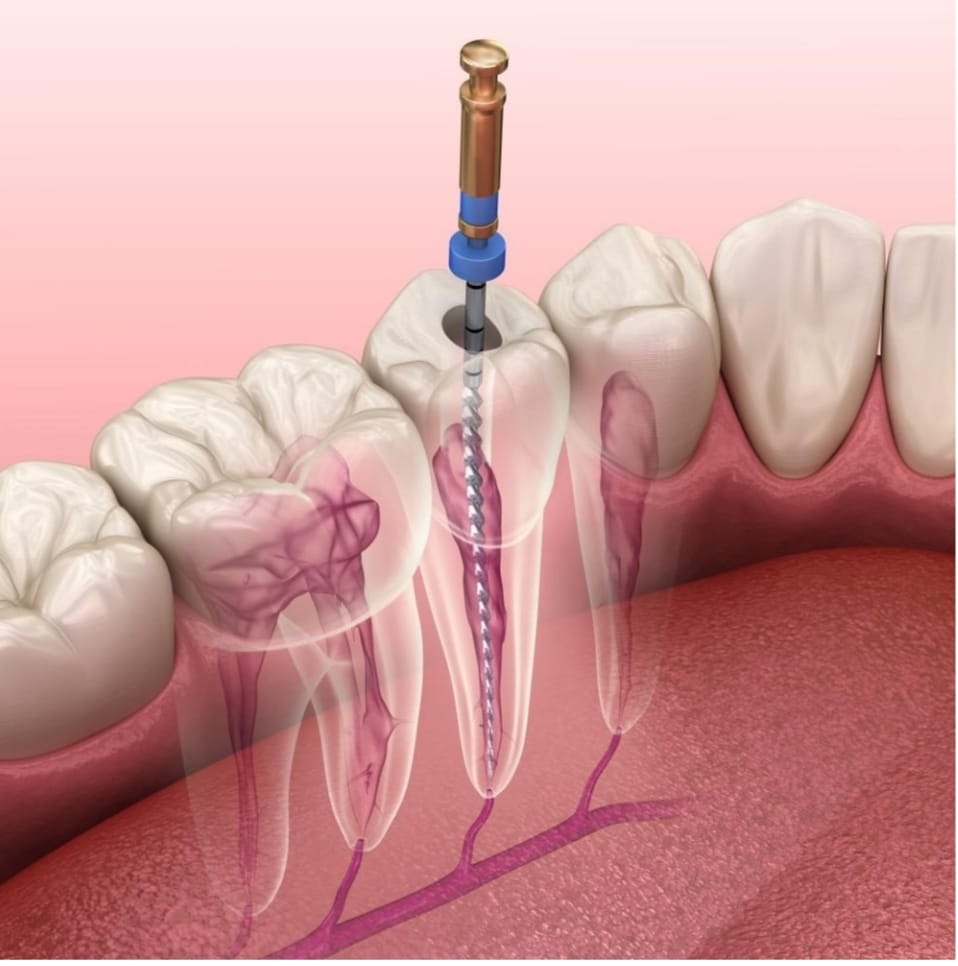

Root Canal Treatment

Root canal therapy is a pain-relieving treatment for infected teeth, removing damaged tissue and preserving the natural tooth structure. Our skilled dentists perform efficient and gentle root canals to restore oral health.